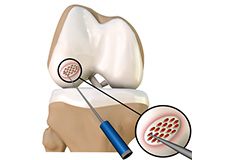

Cartilage Microfracture

Cartilage microfracture is a surgical procedure performed to replace the worn-out articular cartilage with new cartilage.

Chondroplasty

Chondroplasty is a surgical procedure to repair and reshape damaged cartilage in a joint. The procedure involves smoothing degenerative cartilage and trimming any unstable flaps of cartilage.